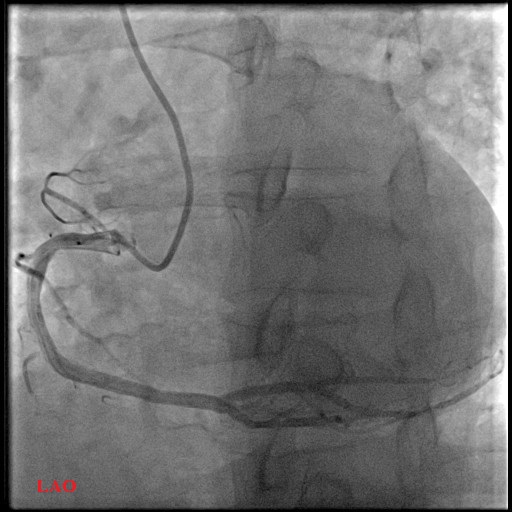

Left Main: moderate distal stenosis 40%

LAD: severe stenosis proximal 95%, TIMI 3

LCx: Small, non-dominant, diffuse disease

RCA: mild proximal disease 20%

LAO RCA.avi